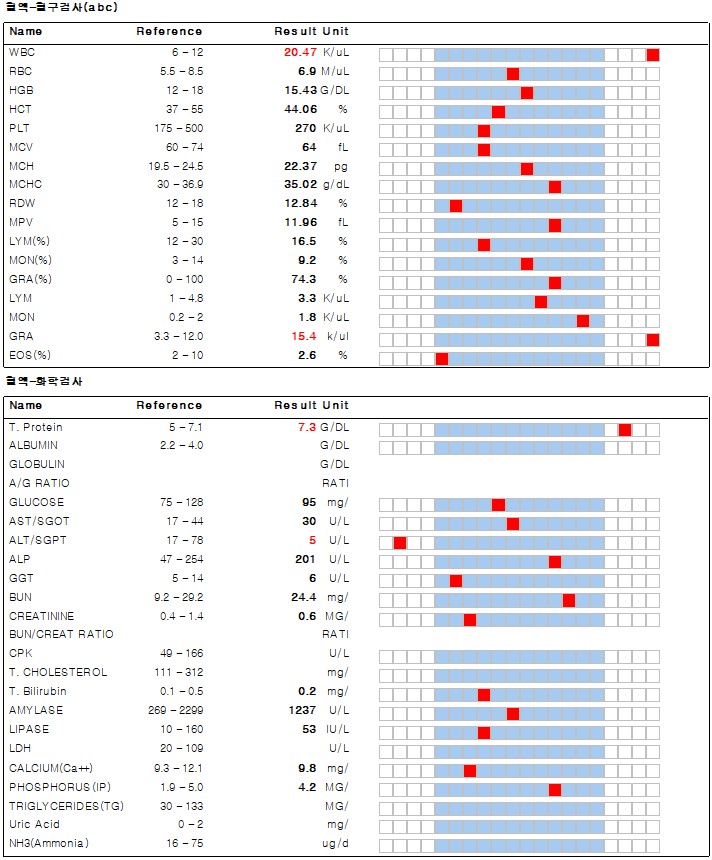

몽*은 설사와 식욕 부진으로 강서구 까치산역 세인트동물병원에 내원하였습니다.기초적인 문진 후 혈액검사를 실시했습니다.

혈액 검사에서는 염증 수치가 상승한 것 이외에는 별다른 소견이 없었습니다.